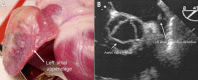

Figures